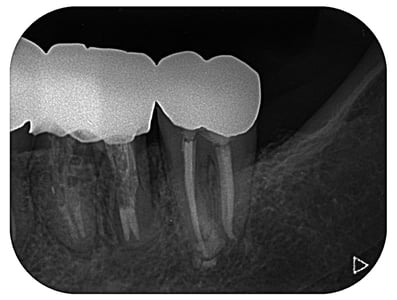

大臼歯の近心根の遠心壁に大きな穿孔が生じていた症例です。体格の良い男性でした。CTによる読影でも、大きな透過像が確認されます。この症例は、チタンメッシュとスーパーボンドを用いて修復しました。

CTでは、頬側の骨が破壊されていないことがわかります。おそらく、治療できるギリギリの時期であったかもしれません。穿孔封鎖後、遠心根も近心根も清掃拡大し、バイオセラミックスにて根尖を封鎖し、グラスファイバーにて築造。上部構造は、メタルのクッション性、メタルマージンの補綴物によるフェルール(帯環)効果を考え、P.F.M.C.としました。

外科的な治療は、第一大臼歯であっても、患者さん個々の頬粘膜の開き具合などのよって可能な場合と不可能な場合もあり、歯牙の部位で可否を決定するべきでないと思っていますし、体格の良い男性でしたが、外科的な処置にはかなり臆病だと感じましたので、非外科的に治療ができてよかったと思っています。

術後、7年経過していますが、問題なく機能しています。

治療期間:約12ケ月(経過観察期間4ケ月を含む)

治療回数:12回(1回/月)

治療費:28万円(破折歯修復+根管治療+支台築造+補綴)※毎回の処置料は別途

リスク:再治療は困難なこと。(そもそも抜歯の症例)

※リスクはどのような治療にも必ずあること。